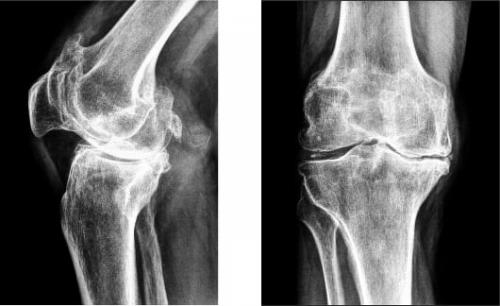

На изображении справа заметно сращение суставной щели.

Коленный сустав является одним из самых крупных и сложных. Ежедневно он подвергается огромной нагрузке, поэтому неудивительно, что периодически он перестает функционировать нормально.Если, причем боль практически постоянная, то необходимо обязательно. Такое патологическое состояние может быть сигналом о развитии одного из, деформирующего сустав. Естественно, необходимо научиться различать ситуации, когда визит к врачу очень нужен. Но отсутствиеили самостоятельная терапия может привести к осложнениям.

Гонартроз коленного сустава на рентгене.